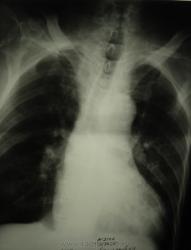

мужчина 1932 г.р. (лежачий пациент, инвалид) привезли со скорой на рентфию ОГК. случайно оказалась рядом и выяснила у сына, что он 3 дня не разговаривает и не кушает. Решила дать глоток бария пока лежит(снимки наспине), вот что получилось....

Образование или инородное тело?

С учетом таких контуров образования возможно лейомиома, но расположение странное, а может образование идет со стороны щитовидной железы?

наверно инородное тело врядли (большое какое то), может из щитовидки что то прорасло??? а может вообще заглоточный абсцесс????

Ну, у стариков инородное тело (кусок мяса) может дать интересные картинки.

Тоже на все 100% соглашаюсь с Валентином Львовичем, в первую очередь необходимо исключать т.н. "мясной завал", а мясо там...сало ...или еще что - дело десятое.....